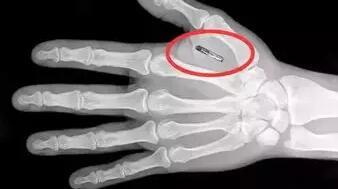

2014年11月,雷蒙德·麦考利做了一个大胆的决定:在自己左手的虎口位置,植入一个微小的芯片胶囊。这样做对人体有多大的风险,目前仍然未有结论。尽管如此,但麦考利没有犹豫:在他看来,人体植入芯片的技术已经成熟。

植入芯片只需要一个小手术,通过探针送入一个2毫米直径、12毫米长的芯片胶囊,整个过程只会比打一枚耳钉略疼一丁点。完成之后,芯片胶囊所在的位置,会产生一个米粒大小的鼓包,但不会带来任何的疼痛或异感。